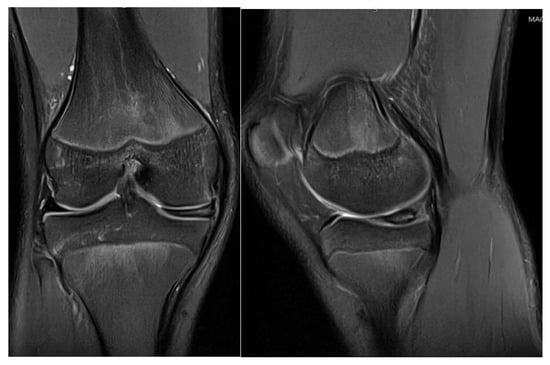

3.3. Case 3—G.L.